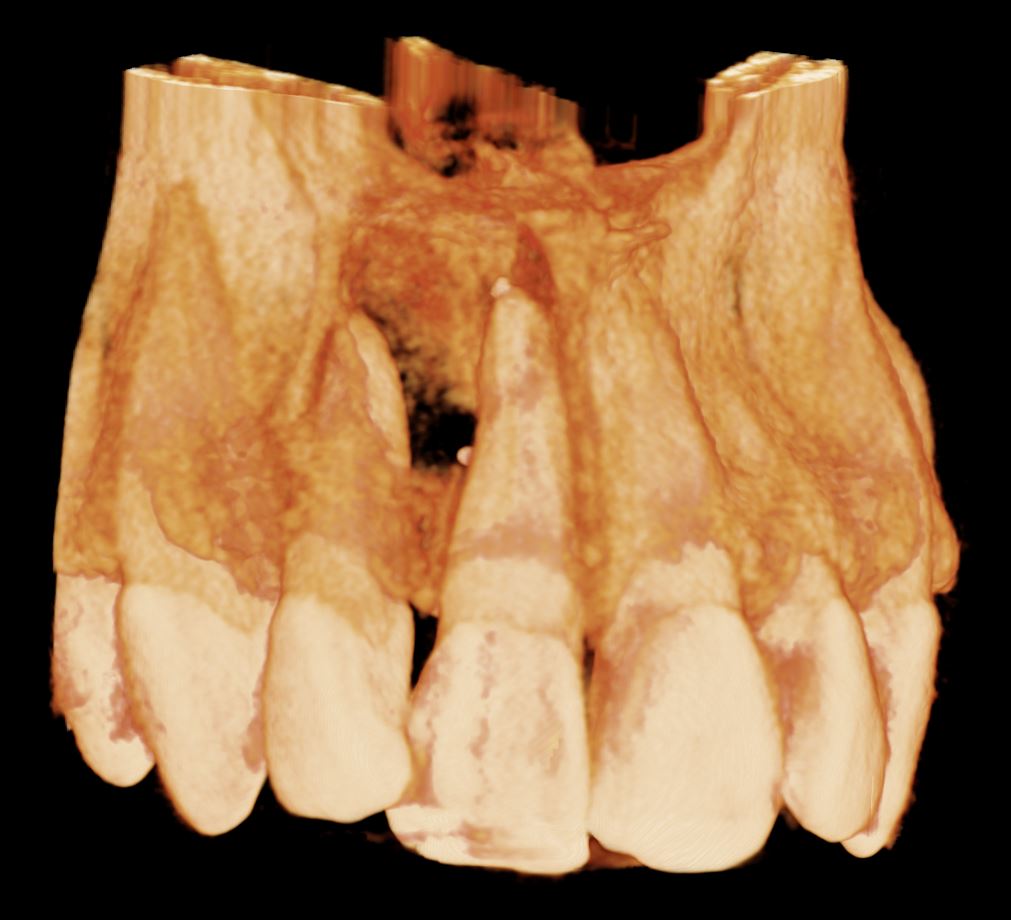

CBCT reconstructed panoramic image

Cropped panoramic, axial and cross section of alveolar ridge UR1 region. UR1 is root filled to the apex with a small amount of extruded filling material inside the lesion (arrow)